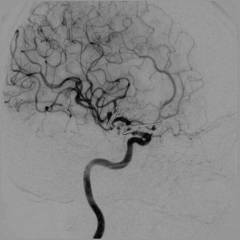

Ангиография головного мозга

Ангиография головного мозга или церебральная ангиография – метод изучения сосудов головы для выявления патологий мозга.

Куда вводят контрастное вещество? Проводят катетеризацию плечевой, локтевой, подключичной или правой бедренной артерии. Катетер продвигают до места ответвления нужного сосуда в мозгу и вводят контрастное вещество в его просвет.

Когда производится рентген съемка? После введения первой порции контраста производят съемку головы в разных проекциях (спереди и сбоку). Снимки сразу же оценивают. Для того чтобы изучить отдаленные от центра отделы сосуда вводят новую порцию контраста и повторяют съемку. После того, как вещество пройдет по тканям, оно появляется в венах. В этот период делают очередную серию снимков. На этом этапе катетер или пункционную иглу удаляют, и исследование считается законченным.